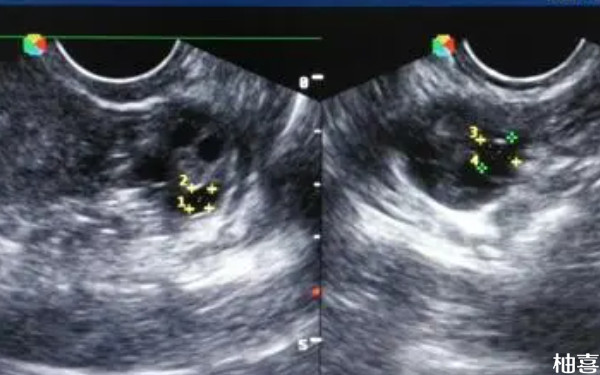

42岁做三代取卵9个成功率高吗?

42岁做三代取卵9个成功率还是相对比较高的,但具体是否能怀孕成功,还需要考虑到胚胎质量,而胚胎是由卵子和精子结合而成,所以卵子和精子的数量、质量在这其中起着至关重要的作用。当女方出现年龄过大、卵巢功能低下、卵巢储备不足等情况时,可能取到的卵子数量就会变少,而且质量差,这都会导致培养成的胚胎质量差。